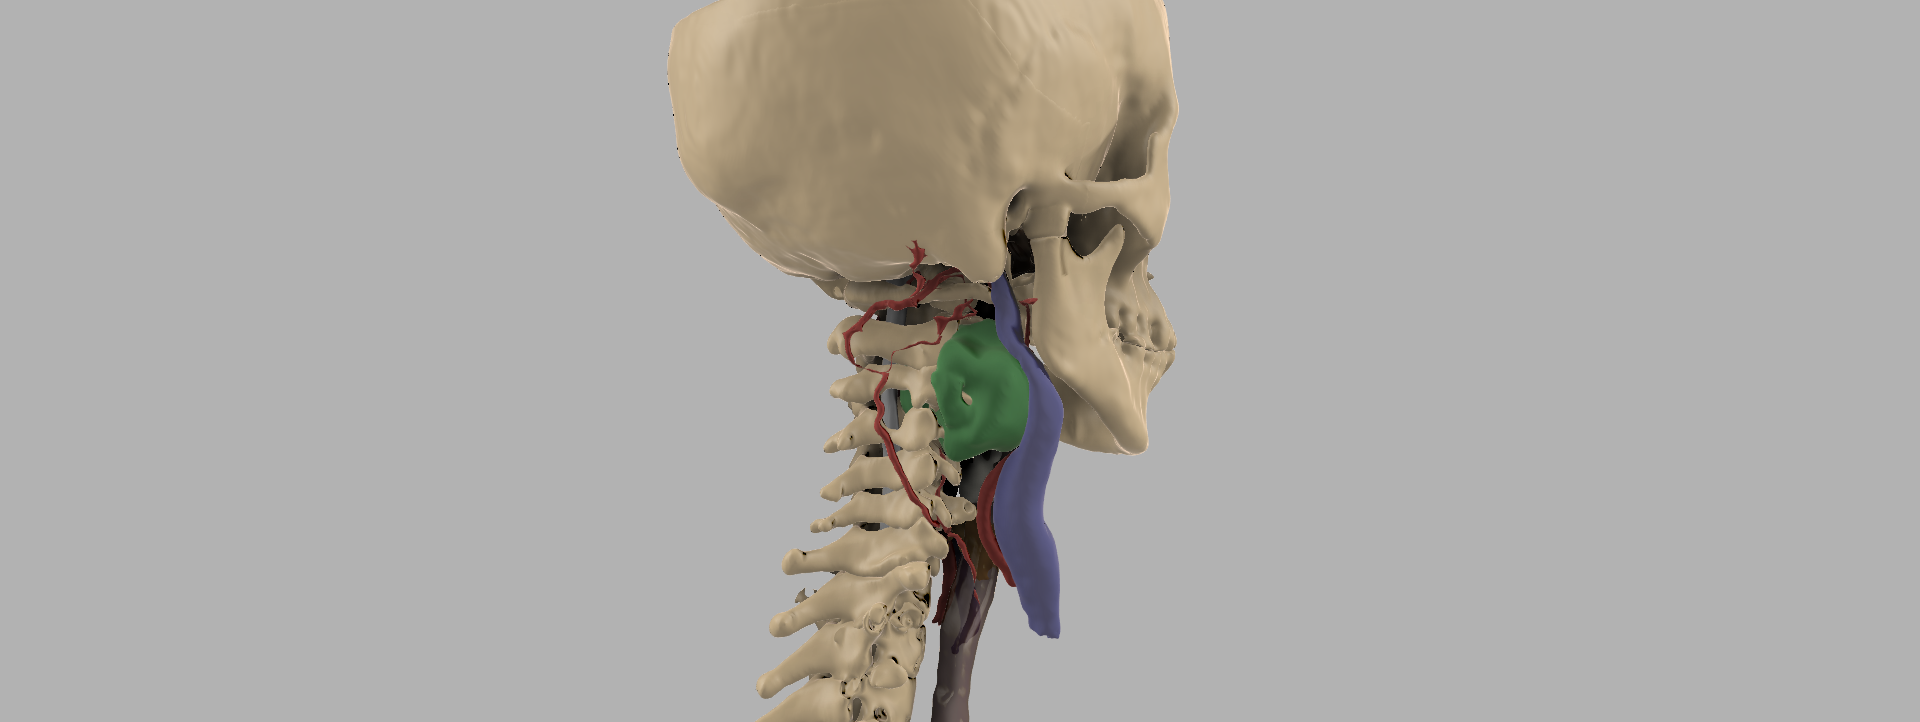

Cordoma en C3

Segmentación anatómica y biomodelo vertebral para analizar la relación de la lesión con estructuras óseas cervicales y acompañar la planificación preoperatoria.

Cordoma en C3

Segmentación anatómica y biomodelo vertebral para analizar la relación de la lesión con estructuras óseas cervicales y acompañar la planificación preoperatoria.